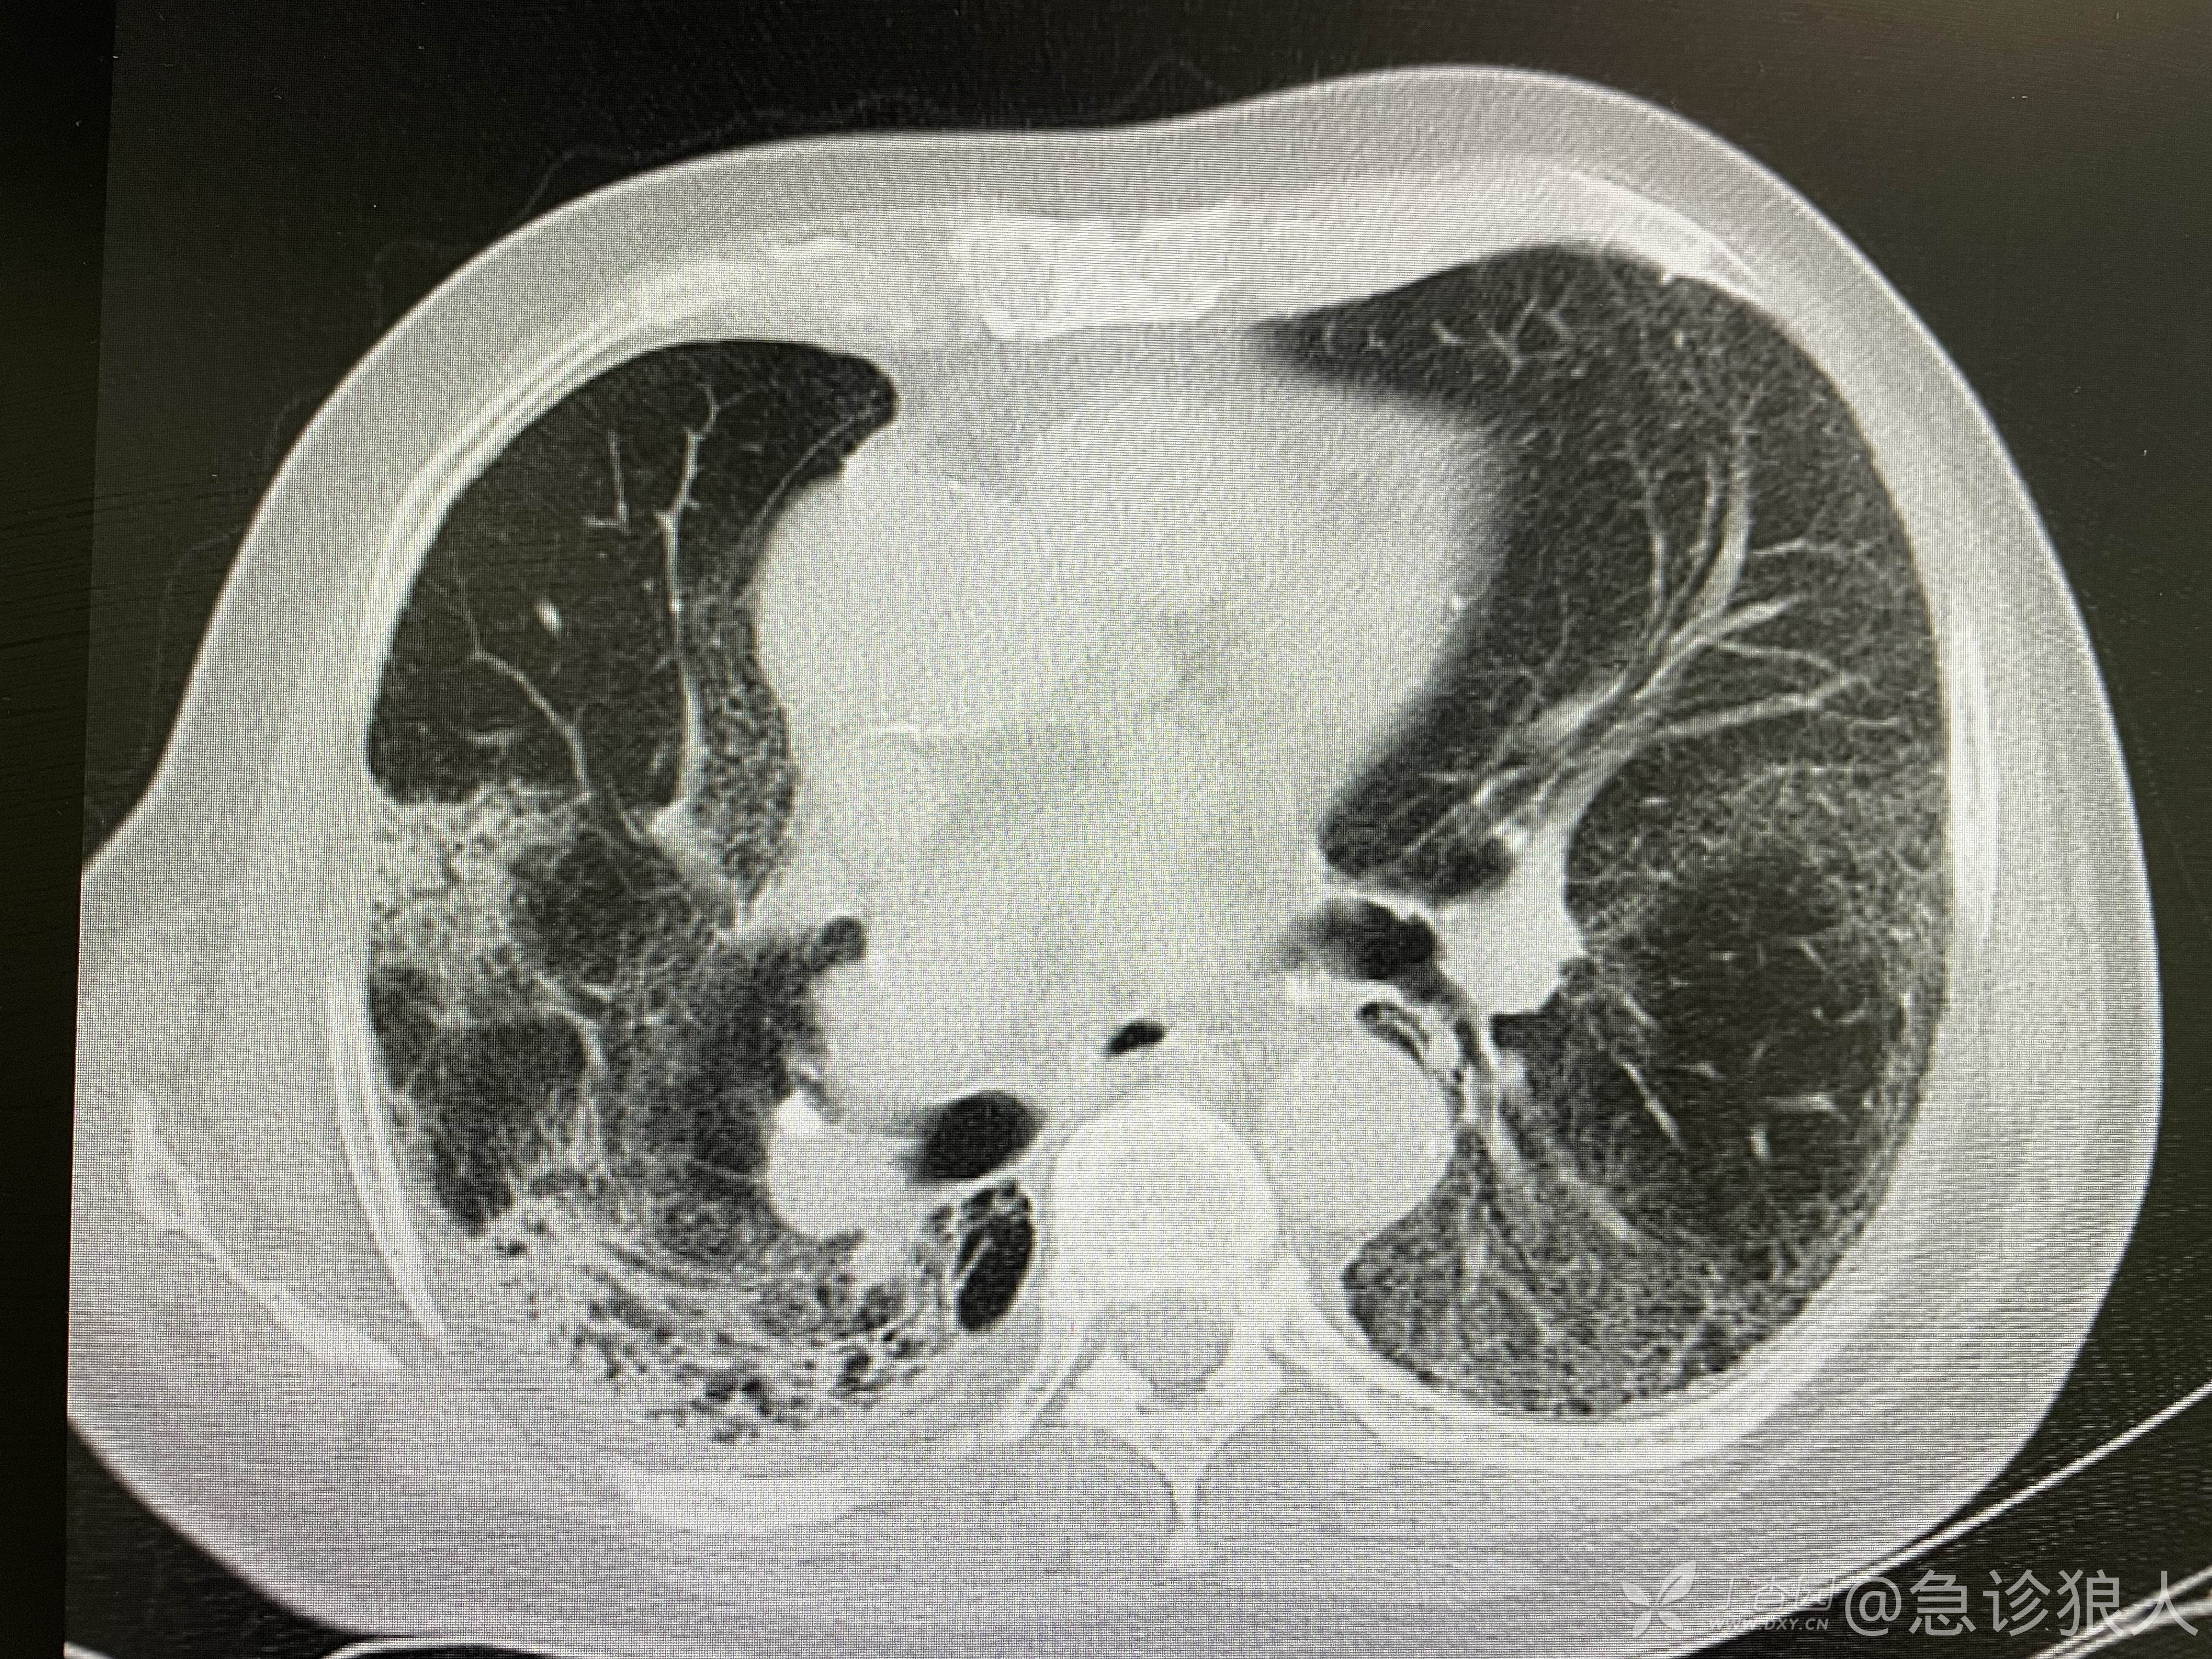

快速走到电脑旁,看了一眼患者的既往Ct!在呼吸科出院时的CT如下: